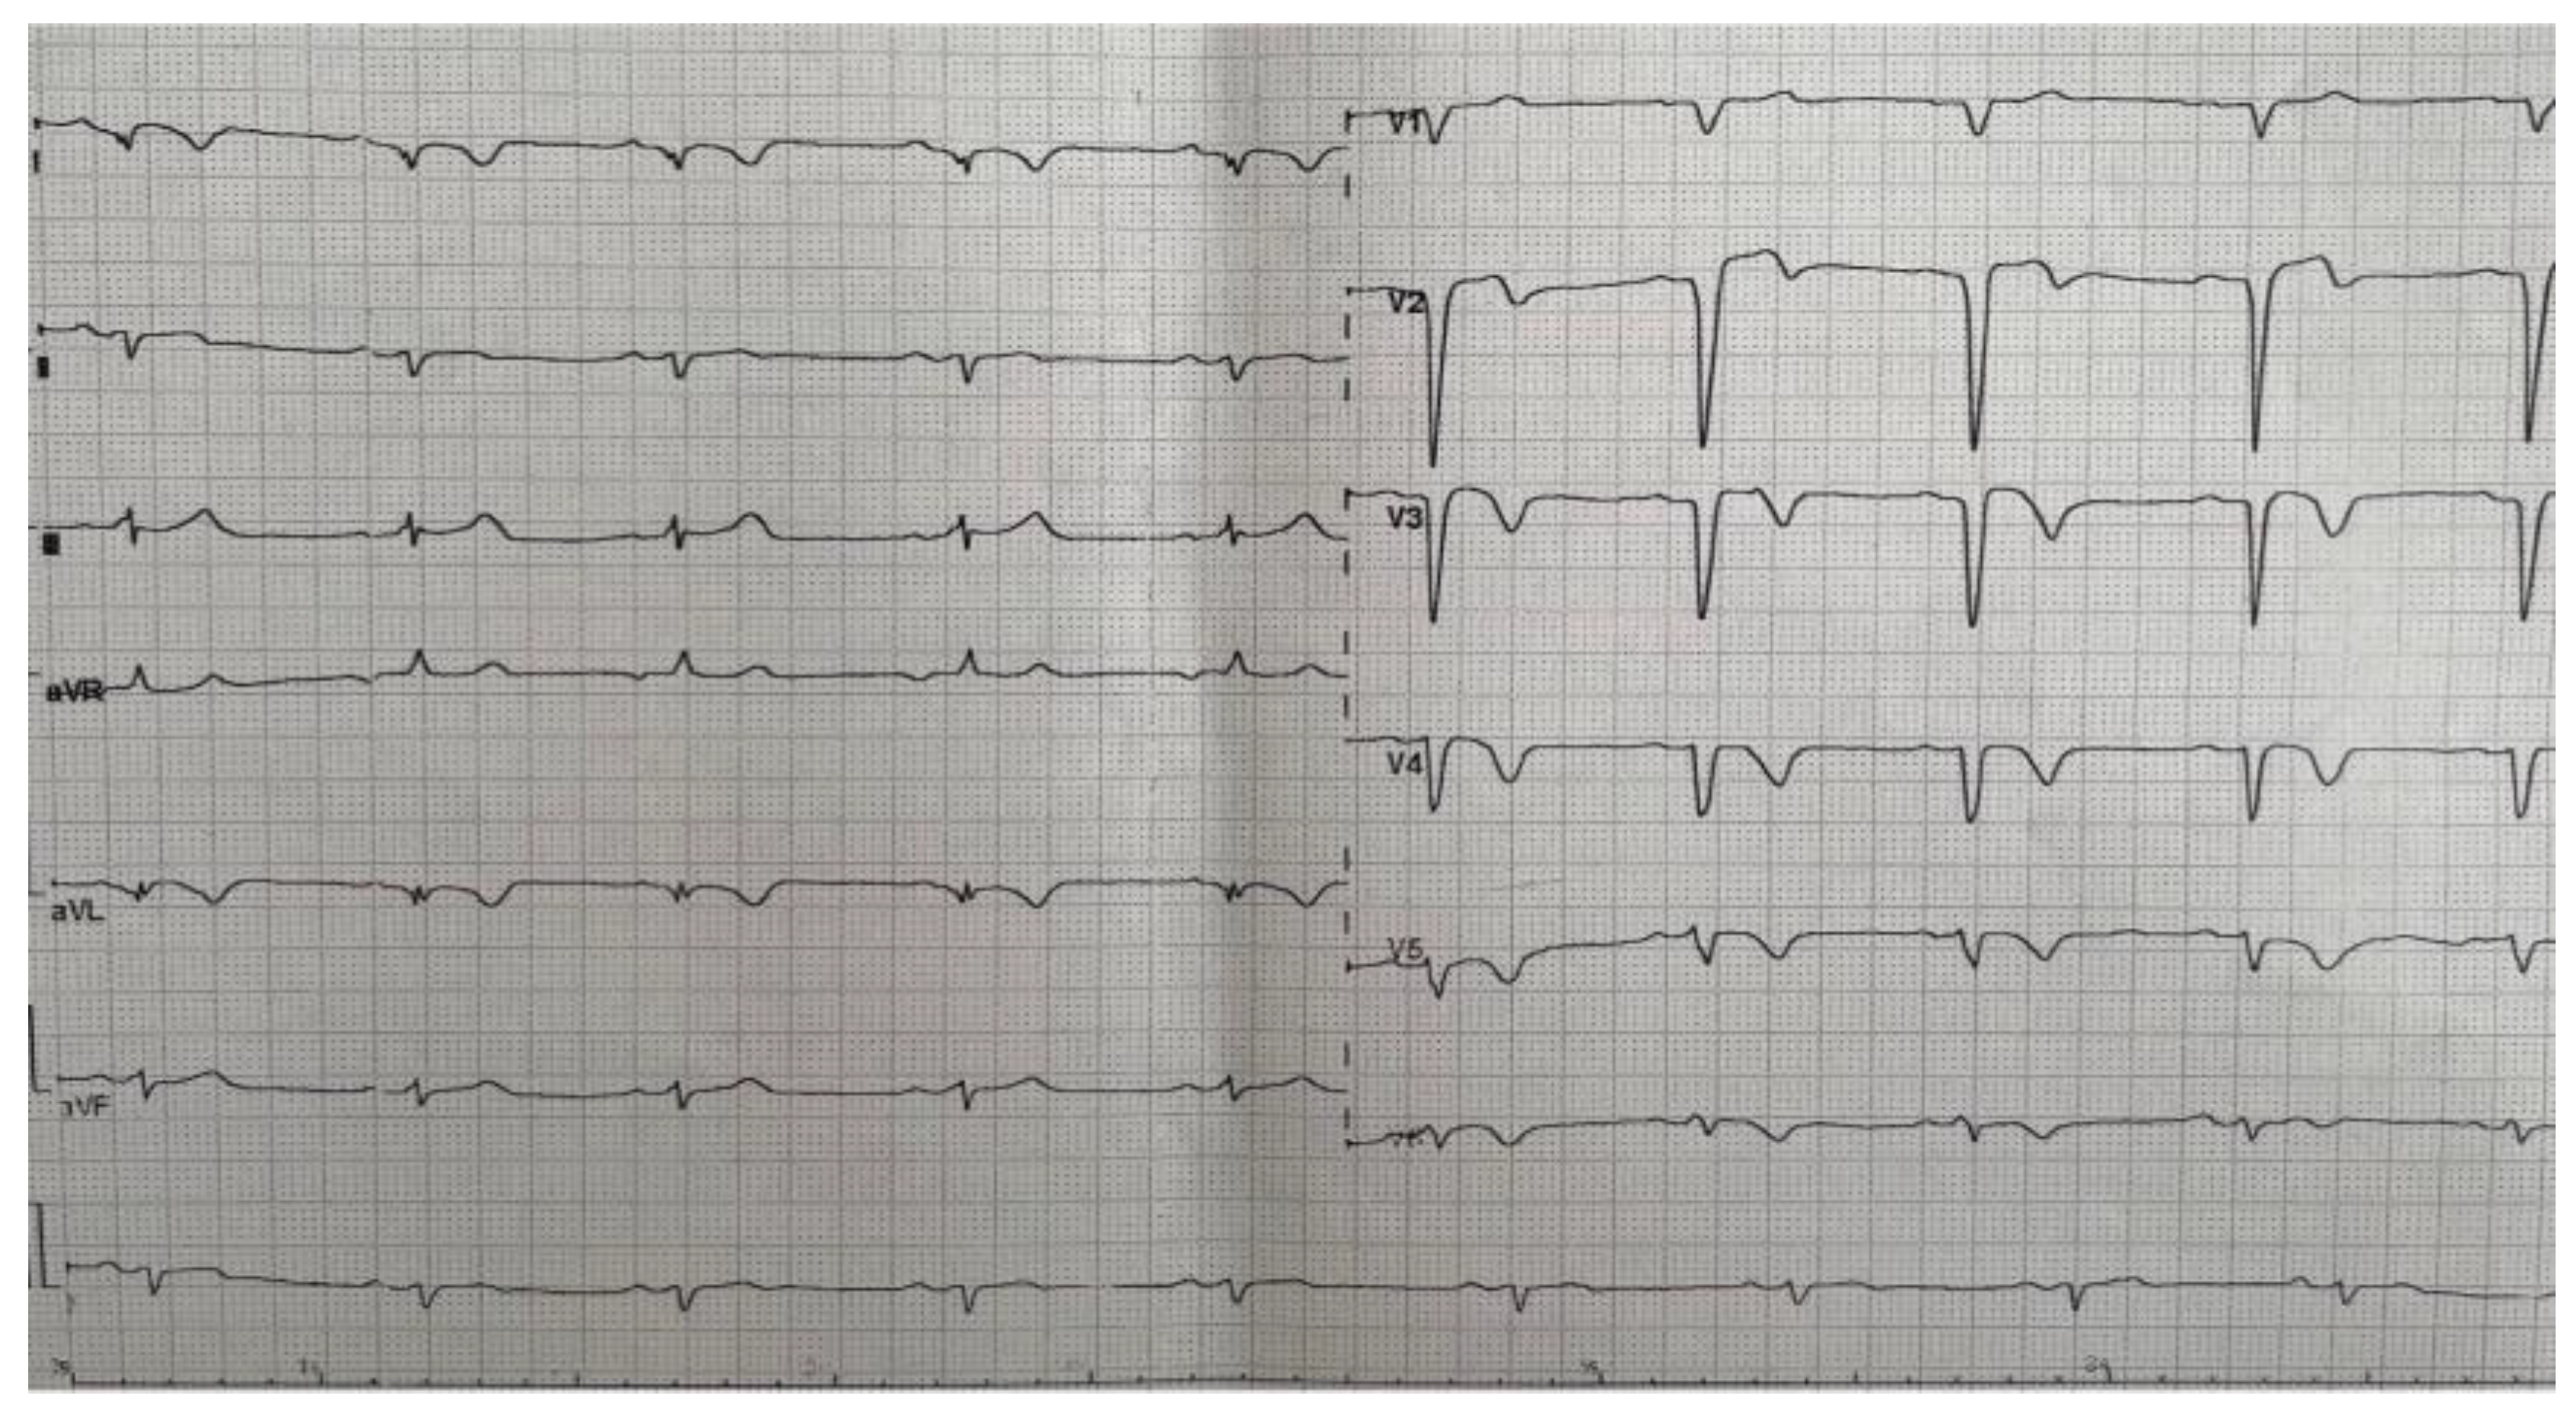

2. Detailed Case Description